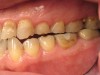

Figure 8 and Figure 9 The right and left side preoperative retracted mirror views.

When viewing his maxillary teeth from an occlusal and lingual view, one can see the erosion and wear (Figure 4, Figure 6, and Figure 7), and it becomes evident just how collapsed he actually is. This patient shows more teeth on his left side and less on the right when smiling, and the shortness and color of his teeth contributes to a definite aging of his smile. Additionally, his lips appear less full without the lip support of the lost tooth structure. The patient had Class I molar relationships on both the right and left sides, and a posterior open bite on his right side in the area of teeth Nos. 4 through 6 (Figure 8 and Figure 9). There was no crowding evident and both arches were found to have lingually inclined teeth, which may have contributed to his wear. It was also noted that his posterior teeth were worn down with a very flat anatomy and lacked proper functional guidance.